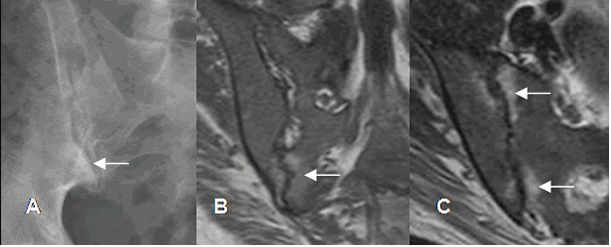

Fig 13 A. Sacroileitis por enfermedad de Crohn.

A: TAC axial. Engrosamiento y captación de la pared, en una asa de intestino delgado, por enfermedad de Crohn. B: RM coronal en T1 y C: RM axial en STIR. Lesiones hipointensas en T1 e hiperintensas en STIR, sobre ambas sacroiliacas, por inflamación aguda.

Fig 13 B. Espondilitis anquilosante.

Rx AP de columna. Presencia de sindesmofitos en la columna dorsolumbar.

Compromiso simétrico de ambas articulaciones sacroiliacas, las cuales están fusionadas.